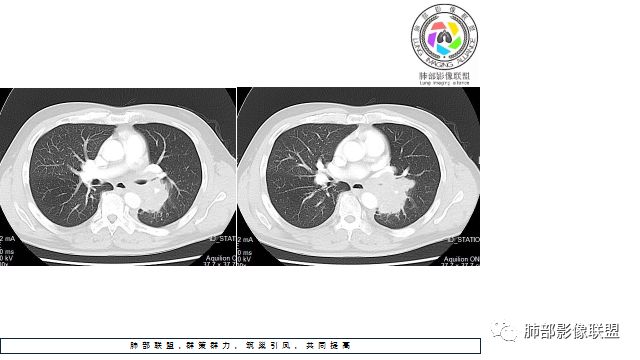

1.左下肺门区巨大肿块,支气管显示不清,轻度阻塞性炎症,没有明显肺不张,提示管腔受压狭窄可能性大于堵塞,这较少见于鳞癌。

2.病灶边缘光滑,未见明显分叶、毛刺,未见明显强化,这符合腺癌影像学特点,却符合神经内分泌癌表现。

3.病灶内密度均匀,轻到中度均匀强化,大病灶未见明显液化坏死区及空洞,不符合鳞癌而符合小细胞肺癌特点。

4.病灶内有肺动脉走形,血管局部受压,未见破坏,病灶乏血供,呈血管包埋或血管造影征;侵袭性力强及破坏力弱、血管漂浮都符合SCLC,所以鳞癌的可能性也不大。

5.左肺门块影或淋巴结肿大,竭力挤兑肺门血管结构,呈冰冻肺门;有时候SCLC可以单独呈现冰冻肺门,而没有没有冰冻纵隔。